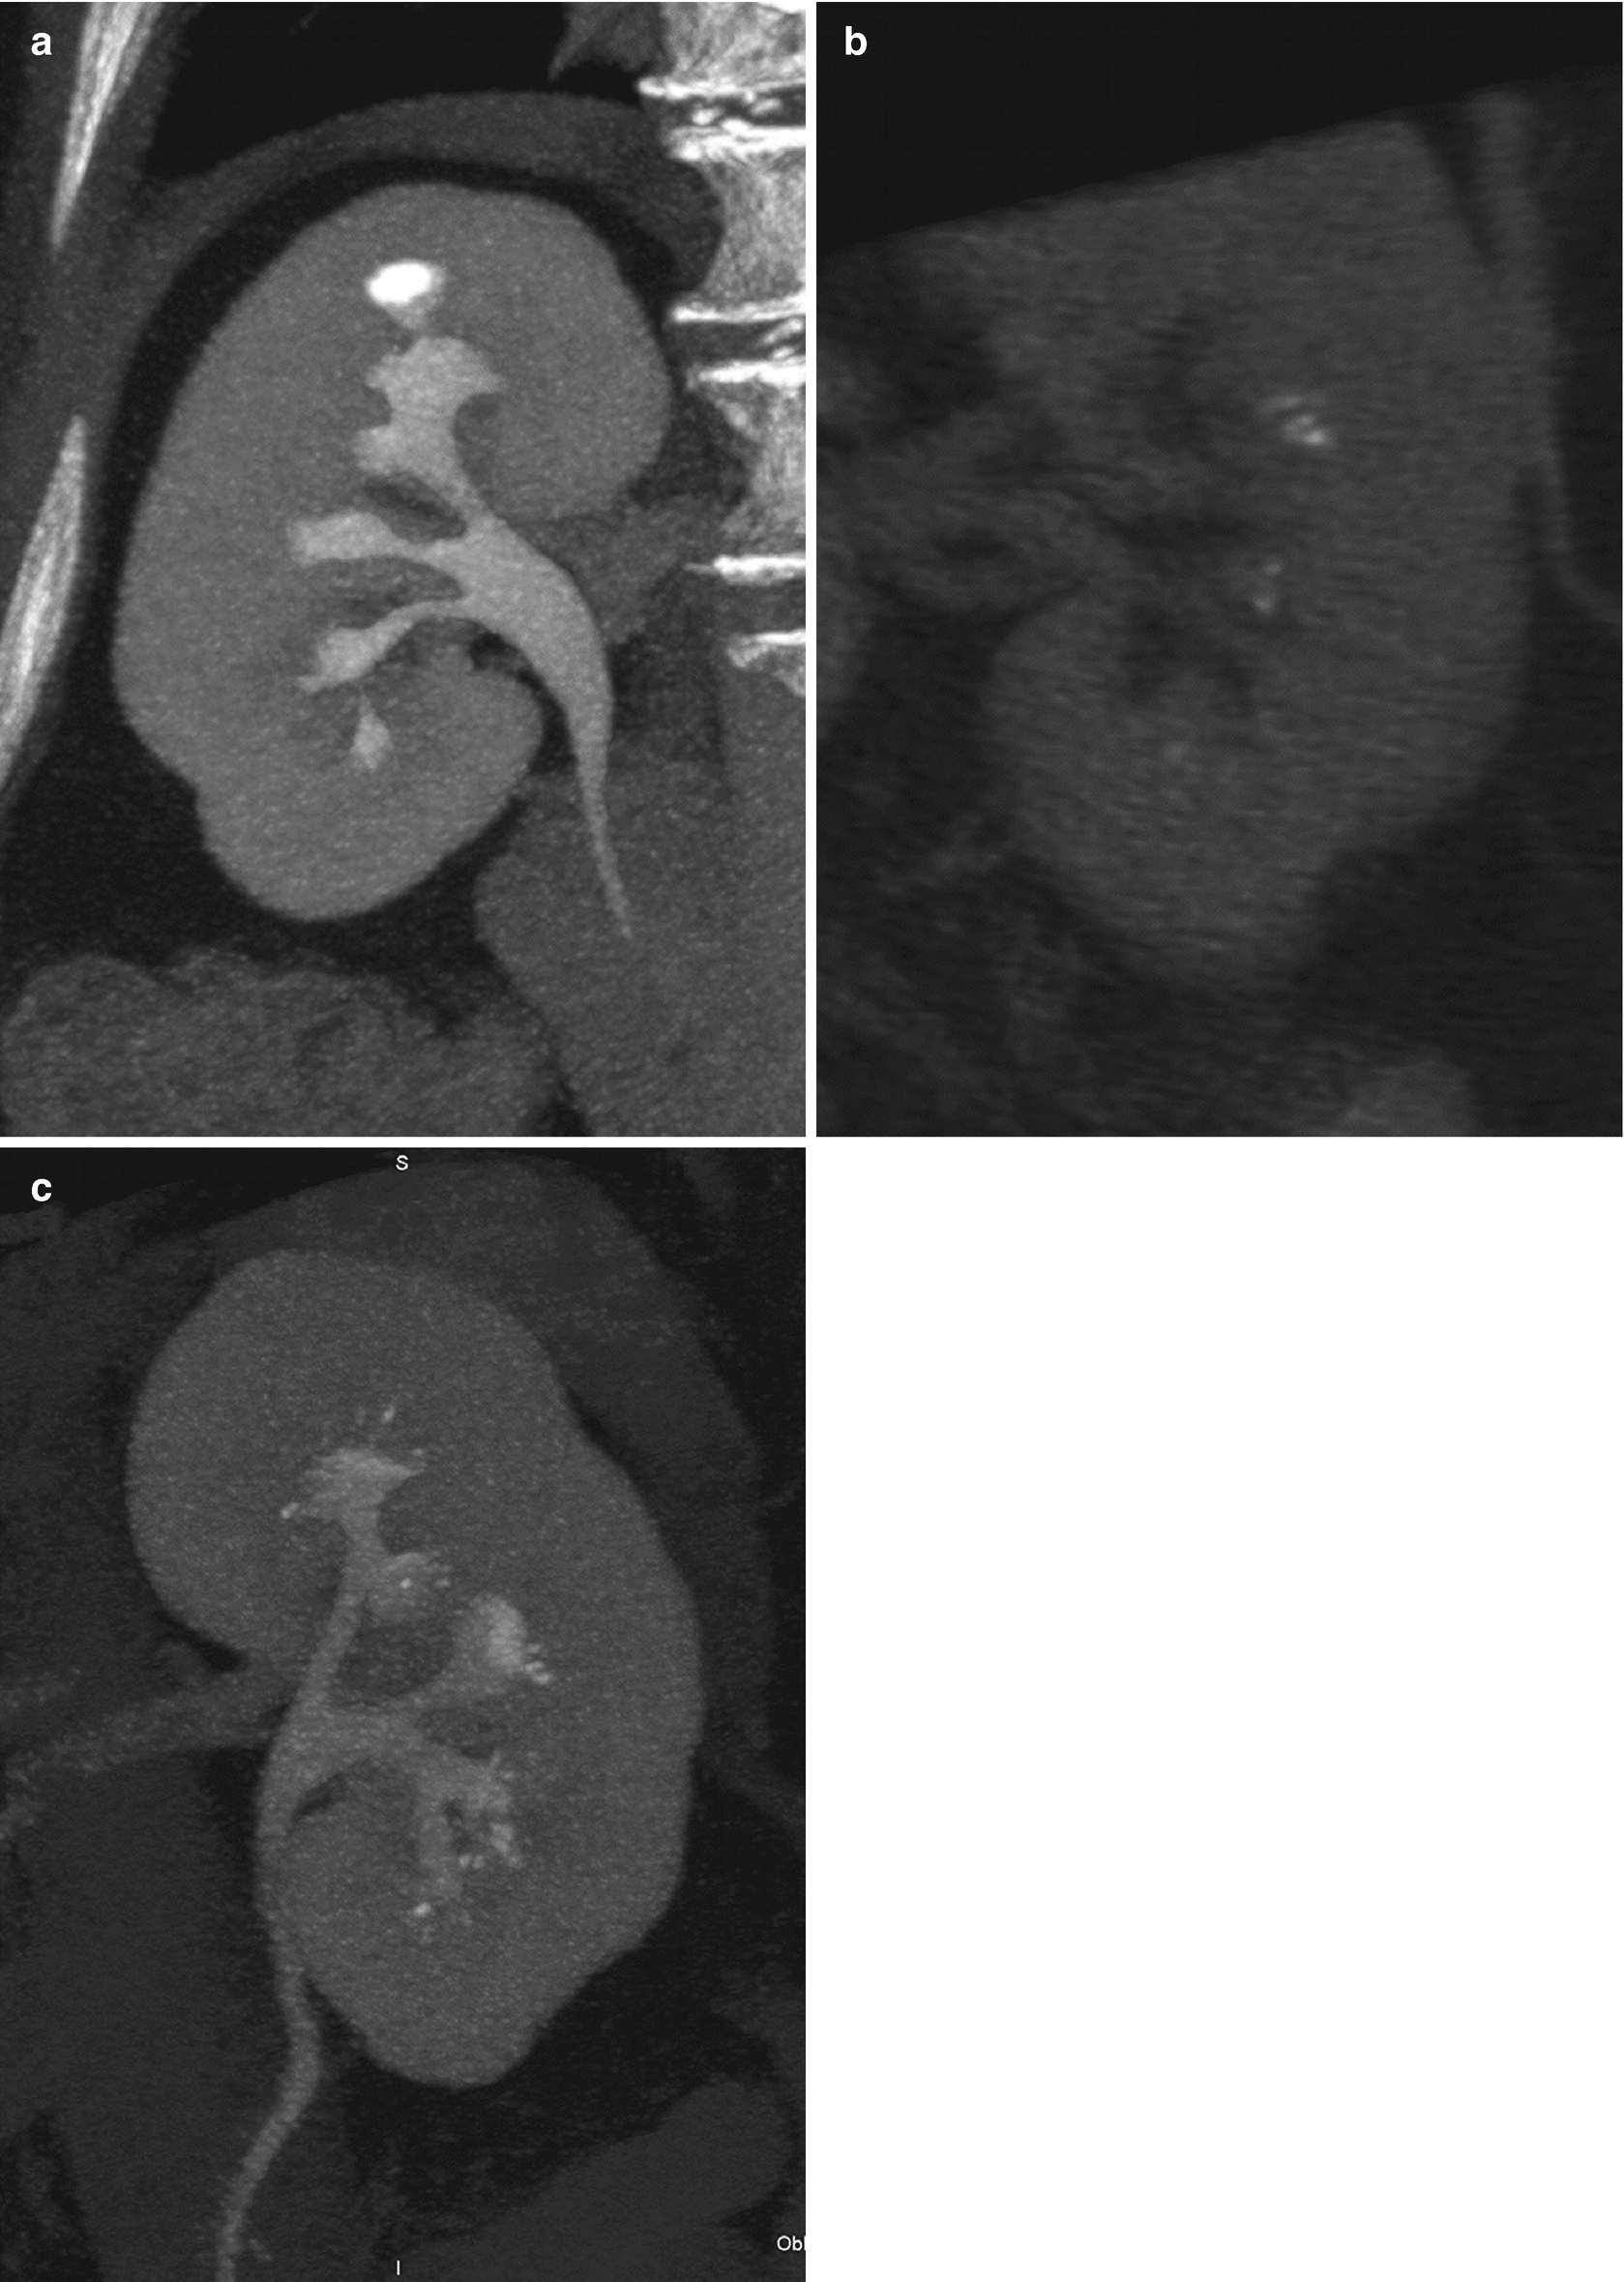

Bilateral Intrarenal Nephrolithiasis

Renal Calculi With Obstruction Radiology Case Radiopaedia Org